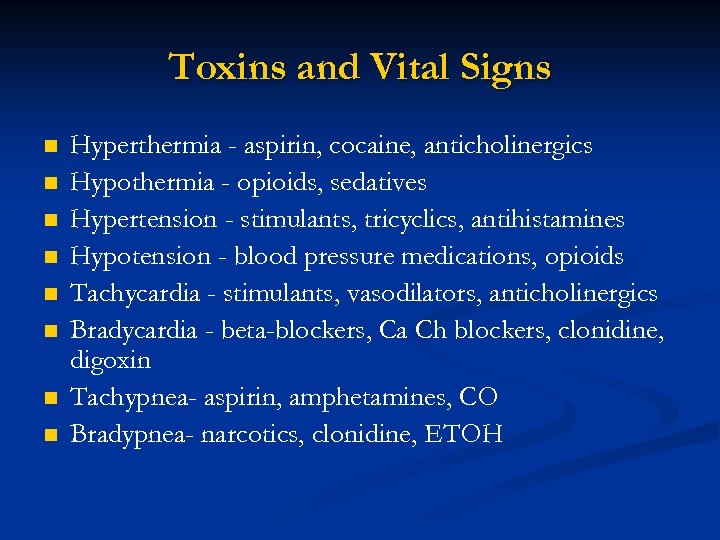

Toxins and Vital Signs n n n n Hyperthermia - aspirin, cocaine, anticholinergics Hypothermia - opioids, sedatives Hypertension - stimulants, tricyclics, antihistamines Hypotension - blood pressure medications, opioids Tachycardia - stimulants, vasodilators, anticholinergics Bradycardia - beta-blockers, Ca Ch blockers, clonidine, digoxin Tachypnea- aspirin, amphetamines, CO Bradypnea- narcotics, clonidine, ETOH

Toxins and Vital Signs n n n n Hyperthermia - aspirin, cocaine, anticholinergics Hypothermia - opioids, sedatives Hypertension - stimulants, tricyclics, antihistamines Hypotension - blood pressure medications, opioids Tachycardia - stimulants, vasodilators, anticholinergics Bradycardia - beta-blockers, Ca Ch blockers, clonidine, digoxin Tachypnea- aspirin, amphetamines, CO Bradypnea- narcotics, clonidine, ETOH